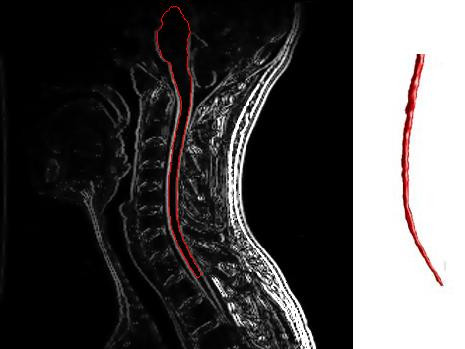

- Quét MRI: Sử dụng thuốc cản quang với MRI cho phép bác sĩ phát hiện các tổn thương hoạt động và không hoạt động trên khắp não và tủy sống của bạn.